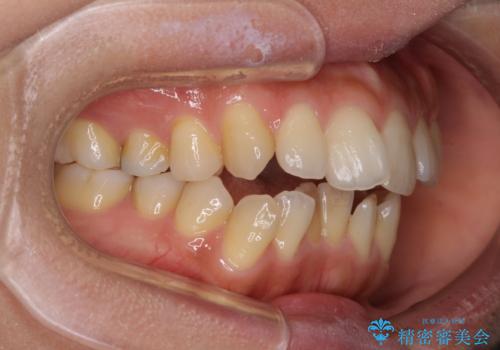

- 前歯のデコボコと咬み合わせを気にして来院された患者様です。

左上奥歯には乳歯が残存しており、後続永久歯は舌側に転位していました。

また、舌の突出癖の影響で上下前歯が接触していないオープンバイトとなっており、奥歯に負担のかかる咬み合わせとなっていました。